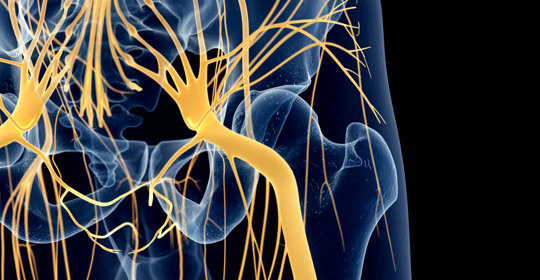

大腦與神經

交感神經亢進:作用、失調症狀與治療

交感神經亢進:中樞位置、遞質型別

交感神經亢進:症狀、診斷與治療

交感神經亢進:就診科室與治療方法

交感神經失養症與複雜區域疼痛症候群、症狀與治療

交感神經亢進:病因、症狀與治療

交感神經亢進:診斷與治療方法